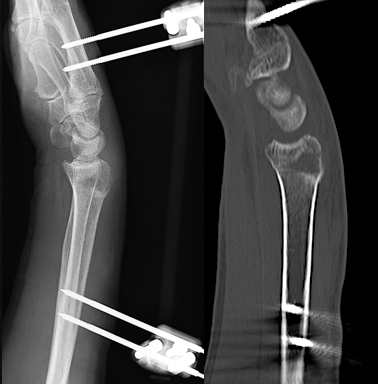

✓​​​創外固定 ー 新しい治療方法

当院では合併症を軽減するため、創外固定という手術を行っております。これは従来の手術のように骨折部を直接開くことなく皮下に挿入したピンを皮膚の外で固定する方法です。2〜3泊で退院することも可能ですし、1〜2週入院のうえリハビリを毎日行うこともできます。骨折部が癒合する4週前後にピンを抜きますが、これは外来で局所麻酔で行い5分程度で終わります。

BGF創外固定器(MES社)

実際の手術例

(手術の傷はピン刺入部のみ)

術後CT(整復されている)